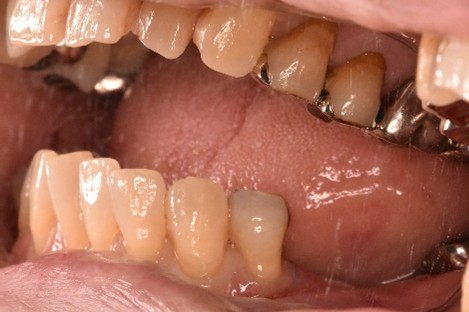

女性Hさん 60代(オールセラミック冠・インプラント)

主訴

右下のブリッジがゆらゆら動く。

治療内容

ブリッジの支台になっている奥の歯が、被せ物の中で虫歯になり、支台の役割を果たさず、前方の歯のみで支えられていました。前方の歯をそのままにして、後方の部分を切り離すと、そのまま取れてきました。中は、虫歯で歯根しか残っていない状況でした。この歯は、根管治療後、単独でオールセラミック冠を被せ、歯のないところにインプラントを埋入しました。

所感

今回の治療法には、次の3つの方法があります。

(1)虫歯になっていた歯の根管治療をし、土台を入れ、また再びブリッジにする。しかし、虫歯になっていたほうの歯は、ブリッジの支台として使うには、心もとなく長持ちしない可能性が高く、今度問題が生じたときには抜歯になる。

(2)虫歯になっていた歯に、単独で被せ物をし、歯のないところに1本だけの部分入れ歯を入れる。取り外しの入れ歯なので、自分の歯のような感覚で噛むことはできない。この方法も歯のない部分の負担を欠損の両側の歯に負担してもらうため、長持ちしない可能性が高い。

(3)虫歯になっていた歯に、単独で被せ物をし、歯のないところにインプラントを埋入する。欠損している部分の負担を前後の歯に負担させないので、歯を守ることができる。また、自分の歯と同じ感覚で食事をすることができる。

患者さんは、3つ目の方法を選択されました。一番長持ちし、これ以上歯を失わないためには、最良の方法だと考えます。

オールセラミック冠(失活歯):¥104,500(税込)

インプラント:¥363,000(税込)

合計:¥467,500(税込)

Before

冠の中で大きな虫歯になり支台の役割を果たしていませんでした。

【インプラント埋入前】

冠はブリッジを切断しただけで取れてきました。軟化象牙質を取り除いたところ、歯根しか残っていない状況で保存できるかどうかのぎりぎりのところでした。

After